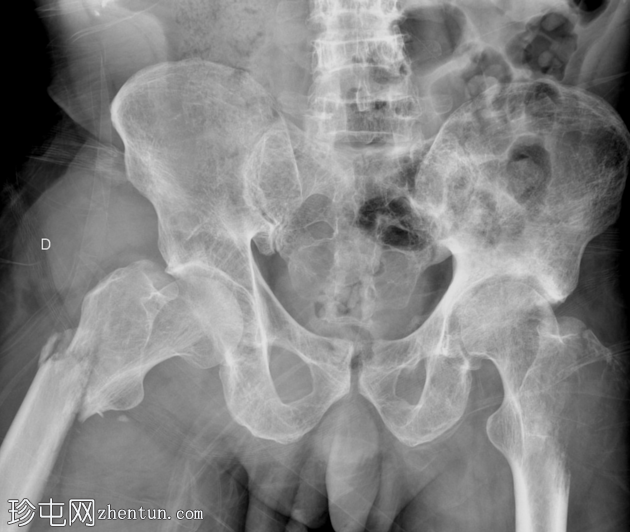

X线片

右股骨转子下骨折。

左侧大转子可见边界不清的大片溶骨性病变,边缘无硬化。

股骨头可见弥漫性边界清晰的溶骨性病变,边缘无硬化。